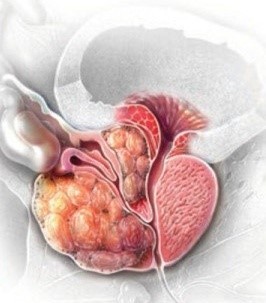

전립선암 수치

전립선암 체크를 통해 전립선암 psa수치를 검사할 수 있습니다. psa는 전립선특이 항원을 말해요. 주로 조기 진단에 사용됩니다. 혈중 psa 수치 증가는 전립선암을 진단하는 데 사용되기 그리해서 건강검진에서 psa 수치를 검사하다 보면 전립선암 진단을 할 수 있습니다.